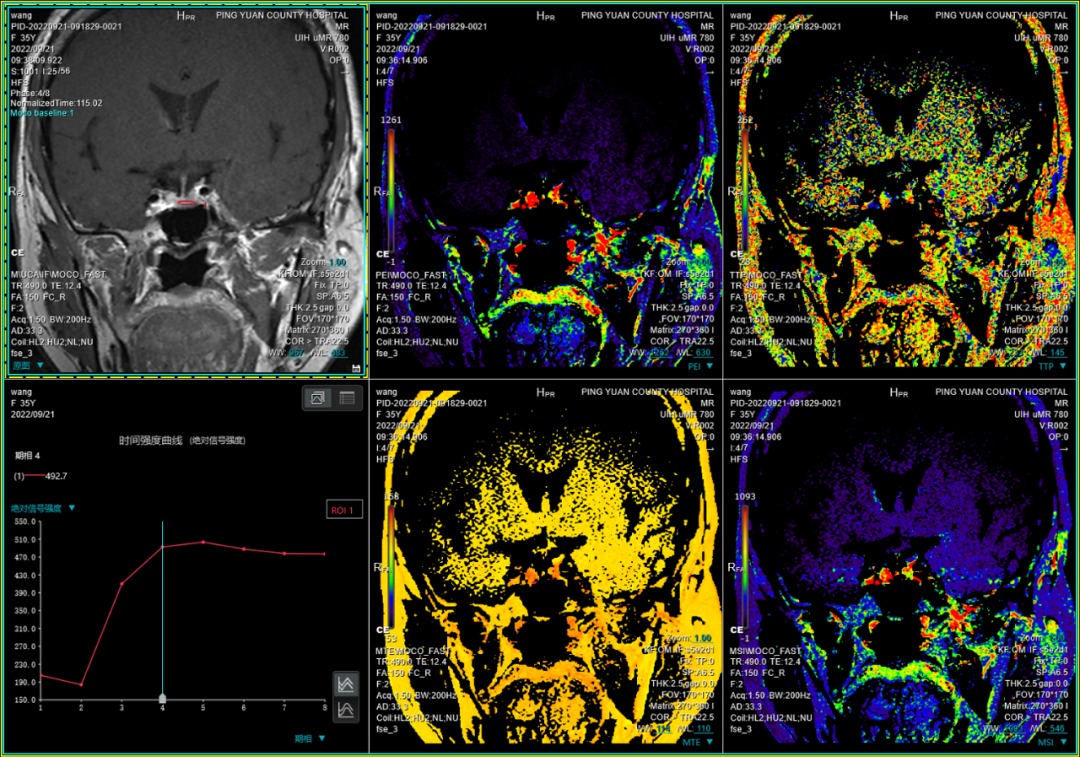

九、垂体动态增强扫描技术:此项检查技术主要应用于垂体瘤的诊断,尤其是应用在垂体微腺瘤的检出上。

联影磁共振怎么样平原县第一人民医院联影uMR780 光梭3.0T磁共振正式投入使用,开启医学影像新时代!_https://www.jmylbn.com_新闻资讯_第26张